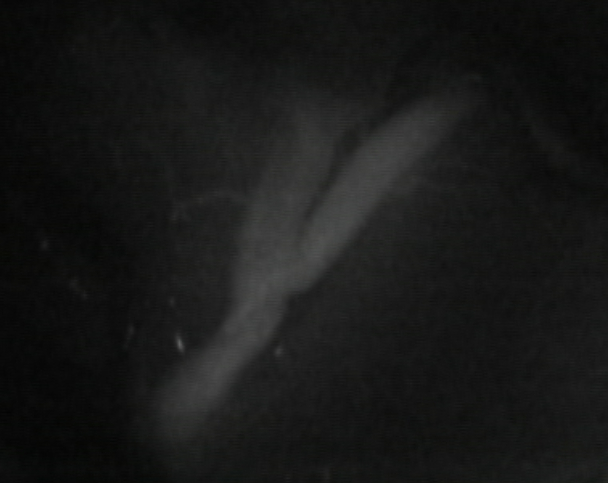

缝完血流通畅:

荧光造影显示血流通畅。挑起来看深入脑沟内的另一端(紧挨着的是根静脉):